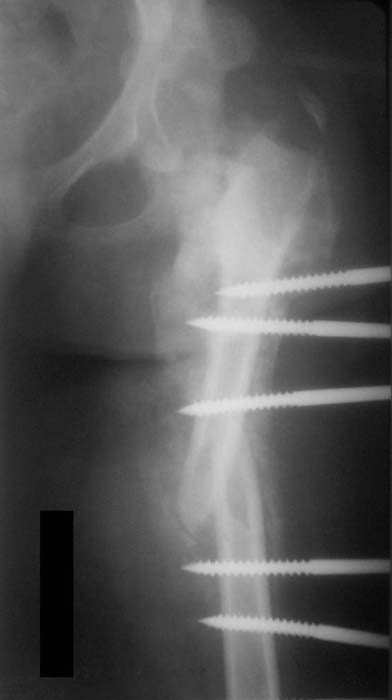

Пациентка 17 лет. В 5-летнем возрасте получила кататравму - осложнённый перелом позвоночника с повреждением спинного мозга в грудном отделе, нижняя параплегия с нарушением функции тазовых органов. Поступила к нам в отделение в сентябре 2007 по поводу патологического перелома левого бедра на фоне хронического остеомиелита бедра. Лечение стержневым аппаратом АВФ, достигнута консолидация. За время лечения развились массивные пролежни крестца и правого бедра с переходом в остеомиелит в/3 правого бедра, сепсис. Выполнено вскрытие гнойника, некрэктомия. Рана велась открыто. В дальнейшем - повторные некрэктомии, дермотензия.

Хотелось бы увидеть рану с разных ракурсов и рентгенограммы таза и бедра. Тогда можно создать представление о площади и глубине раны.

>Можно наложить простейший аппарат таз-бедро и подвесить больного

Такая мысль тоже приходила. Не решились, так как:1.Выраженный остеопороз костей таза и бедра, больная тучная - высок риск того, что стержни не выдержат. 2.Сейчас больная передвигается в инвалидном кресле - хоть какая-никакая, а динамизация. Если лишить её этой возможности - застойная пневмония со всеми вытекающими...